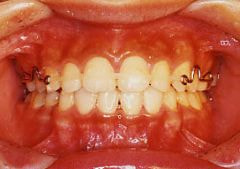

金属(メタル)ブラケット

メリット

* 装置についた汚れがわかりやすい

* 歯みがきしやすい

デメリット

* 目立ちやすい